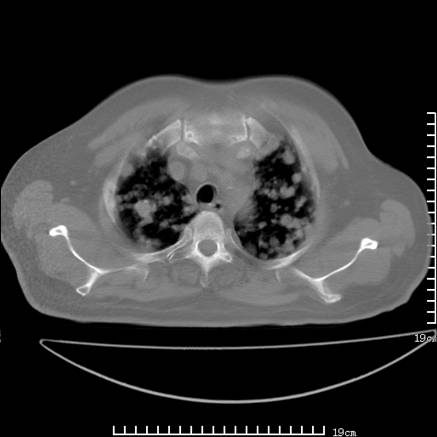

张男,75岁,干咳半年余,小便不利二年,b超检查前列腺增大,未见明显肿块;前列腺癌血生化检查多项指标明显增高。

双肺内多发转移瘤,纵膈淋巴结转移。来源前列腺?建议盆腔mri进一步检查。

双肺转移满了。

两肺广泛转移瘤。